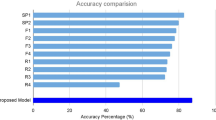

In both models, CAM was able to identify the pathologic region on OCT successfully, based on the generated heat map (Fig. 4). Additionally, in the second model, the learning stabilized faster with transfer learning than with CNN (Fig. 5).

Comparison of the necessary number of epochs for convergence of the training loss, and classification performance, between the transfer-learning model and the CNN of the same architecture without transfer learning. In the second model, for classification of AMD images into with or without exudative changes, learning stabilized faster when using transfer learning. CNN convolution neural network, AMD age-related macular degeneration, AUROC area under the receiver operating characteristic curve